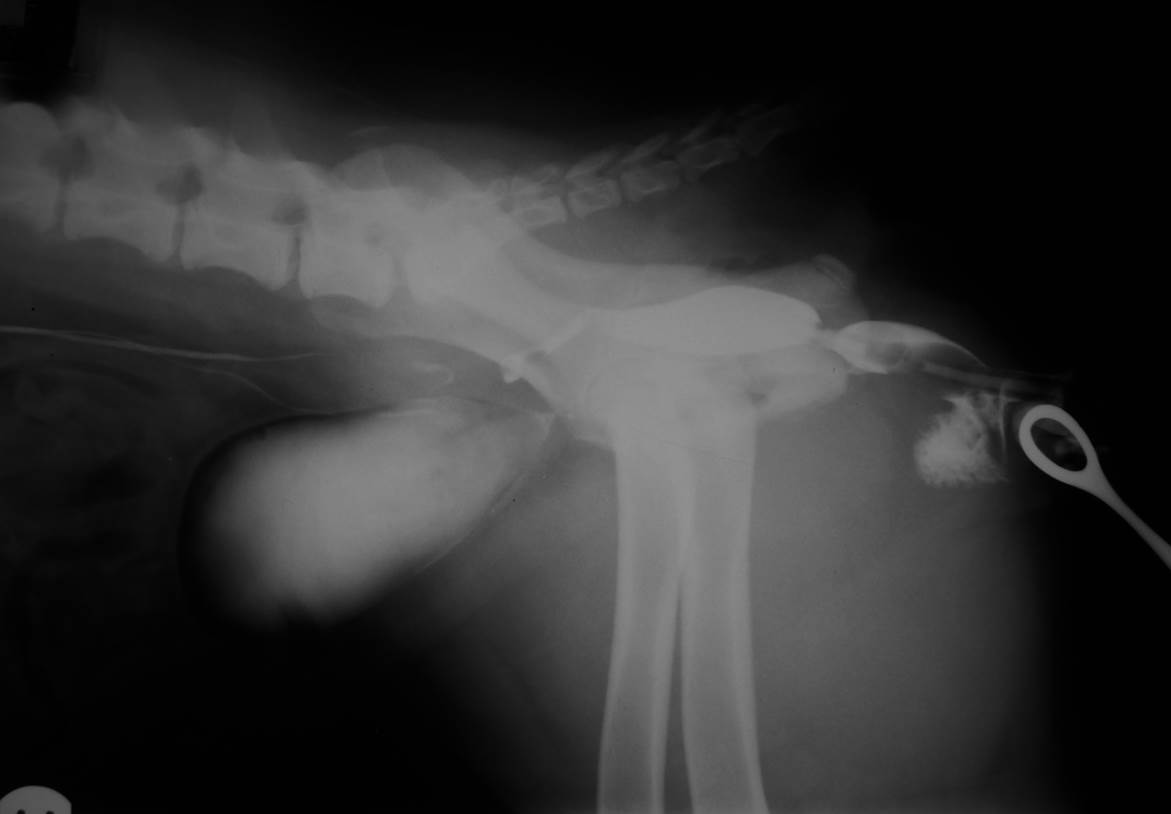

Case Flossie

Discuss this case?

•Normal IVU & RVU showing no evidence of

–ectopic ureter

–megaureter

–hydronephrosis

–bladder hyoplasia

–urethral anomaly

–uroliths